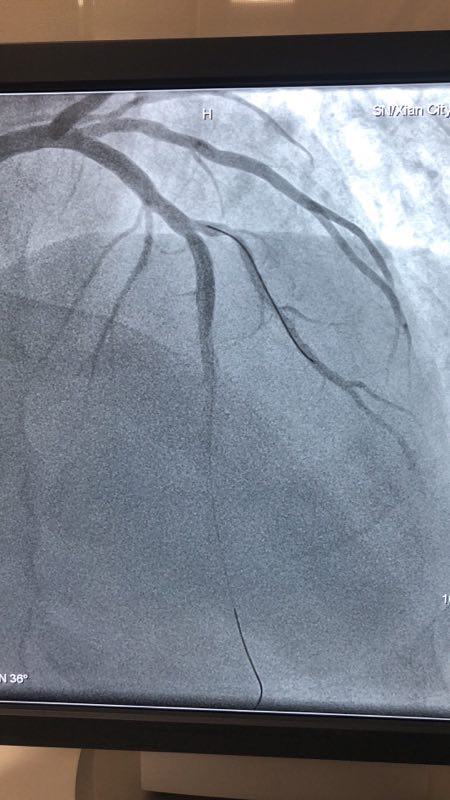

2018年12月27日下午,啄木鸟 CCU病区成功应用药物涂层球囊扩张术救治一名支架内再狭窄患者。

此例患者,男性,56岁,11年前因心绞痛在西京医院行冠状动脉造影检查后于D1对角支置入1枚支架治疗。术后患者口服“阿司匹林肠溶片、氯吡格雷、阿托伐他汀”等药物治疗1年后自行停药,并有长期大量吸烟史。2018年12月24日患者突发胸痛、胸闷,急来啄木鸟 就诊。急诊行冠状动脉造影检查提示D1对角支原支架内再狭窄70%-90%。急救中心主任张誉洋副主任医师考虑到第一对角支管径较小,于原支架内再次置入支架引起再狭窄的风险极大,遂建议应用药物涂层球囊扩张术治疗D1对角支原支架内狭窄。与患者充分沟通后,于12月27日行冠脉药物涂层球囊PTCA术治疗,造影显示血管开通情况良好,术后患者症状明显改善。

冠脉药物涂层球囊扩张术,由于不需置入外来物质,因此可以避免置入支架的很多缺陷。既达到“支架”扩张血管的目的,同时还能避免术后血管再狭窄,可谓一举两得。该技术可应用于小血管病变和不能耐受长期强化抗血栓治疗的患者,随着临床应用的增加可为更多患者带来福音。